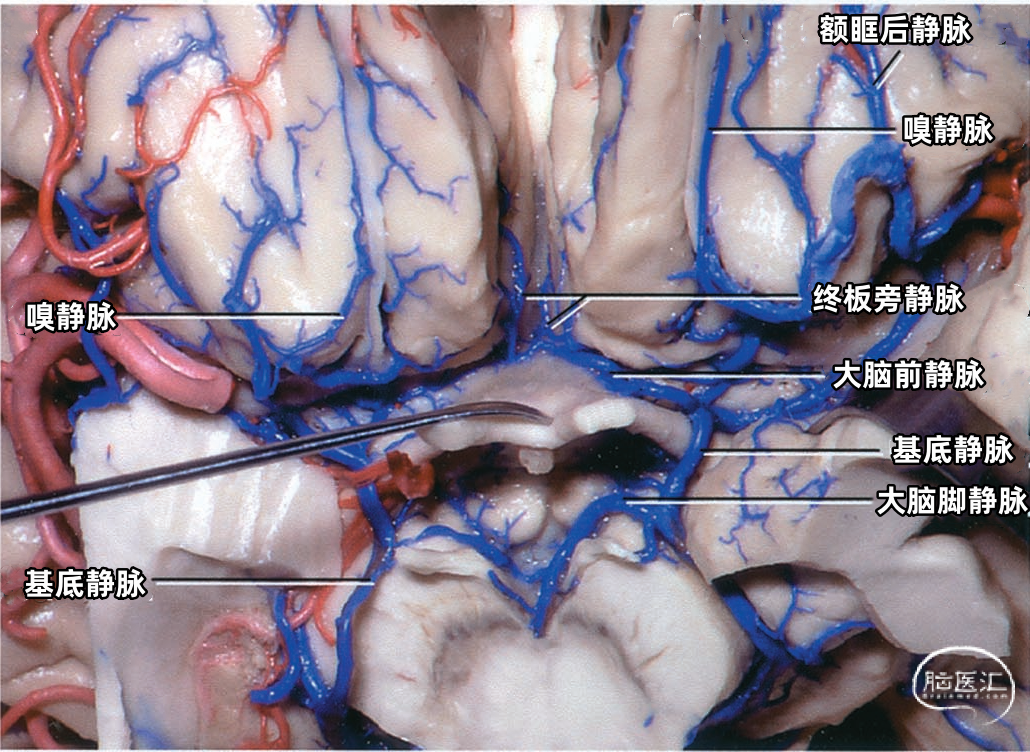

额叶底面(蓝色)由额极静脉、眶额前静脉、眶额后静脉,嗅静脉和终板旁静脉引流。 颞叶底面(绿色)由颞底前静脉、颞底中静脉、颞底后静脉、海马前静脉、钩回静脉、颞内侧静脉、颞外侧裂静脉。

额叶底面的静脉按引流方向由两种蓝色标出:浅蓝色为前组静脉,进入上矢状窦。深蓝色为后组静脉,进入基底静脉前端。额底静脉的前组是眶额前静脉;后组包括眶额后静脉和嗅静脉。 颞叶底面的静脉按引流方向由两种绿色标出:深绿色标注的静脉向外侧走行汇入小脑幕窦。浅绿色标注的静脉向内侧走行汇入基底静脉。向外侧走行的颞底静脉包括颞底前静脉、颞底中静脉、颞底后静脉;向内侧走行的颞底静脉包括海马前静脉、钩回静脉、颞内侧静脉。 枕叶底面只有一支即枕下静脉,由紫色标出,汇入小脑幕窦。大脑内静脉汇入Galen静脉。

▼1.额叶

嗅静脉、终板旁静脉、大脑前静脉和额眶后静脉汇合于基底静脉前端。

下图示左侧前穿质下方区域的放大观。嗅静脉、大脑前静脉、额眶后静脉、外侧裂深静脉汇集形成基底静脉。脑室下静脉在大脑脚后缘汇入基底静脉。